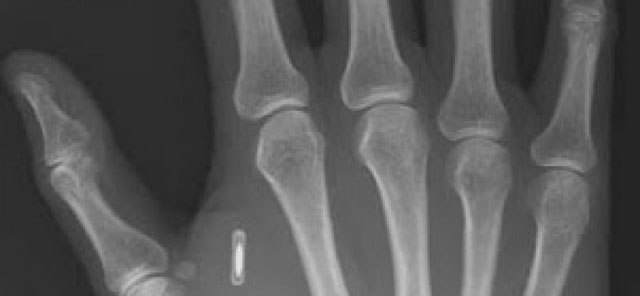

Mikroçipler sayesinde işçiler kapıları açabiliyor, kantinde ödeme yapıyor ya da fotokopi makinesini kullanabiliyor. Radyo frekanslı kimlik tanıma sistemi (RFID) ile işçilerin ellerinin arkasına yerleştirilen çipler bir pirinç tanesi boyutunda.